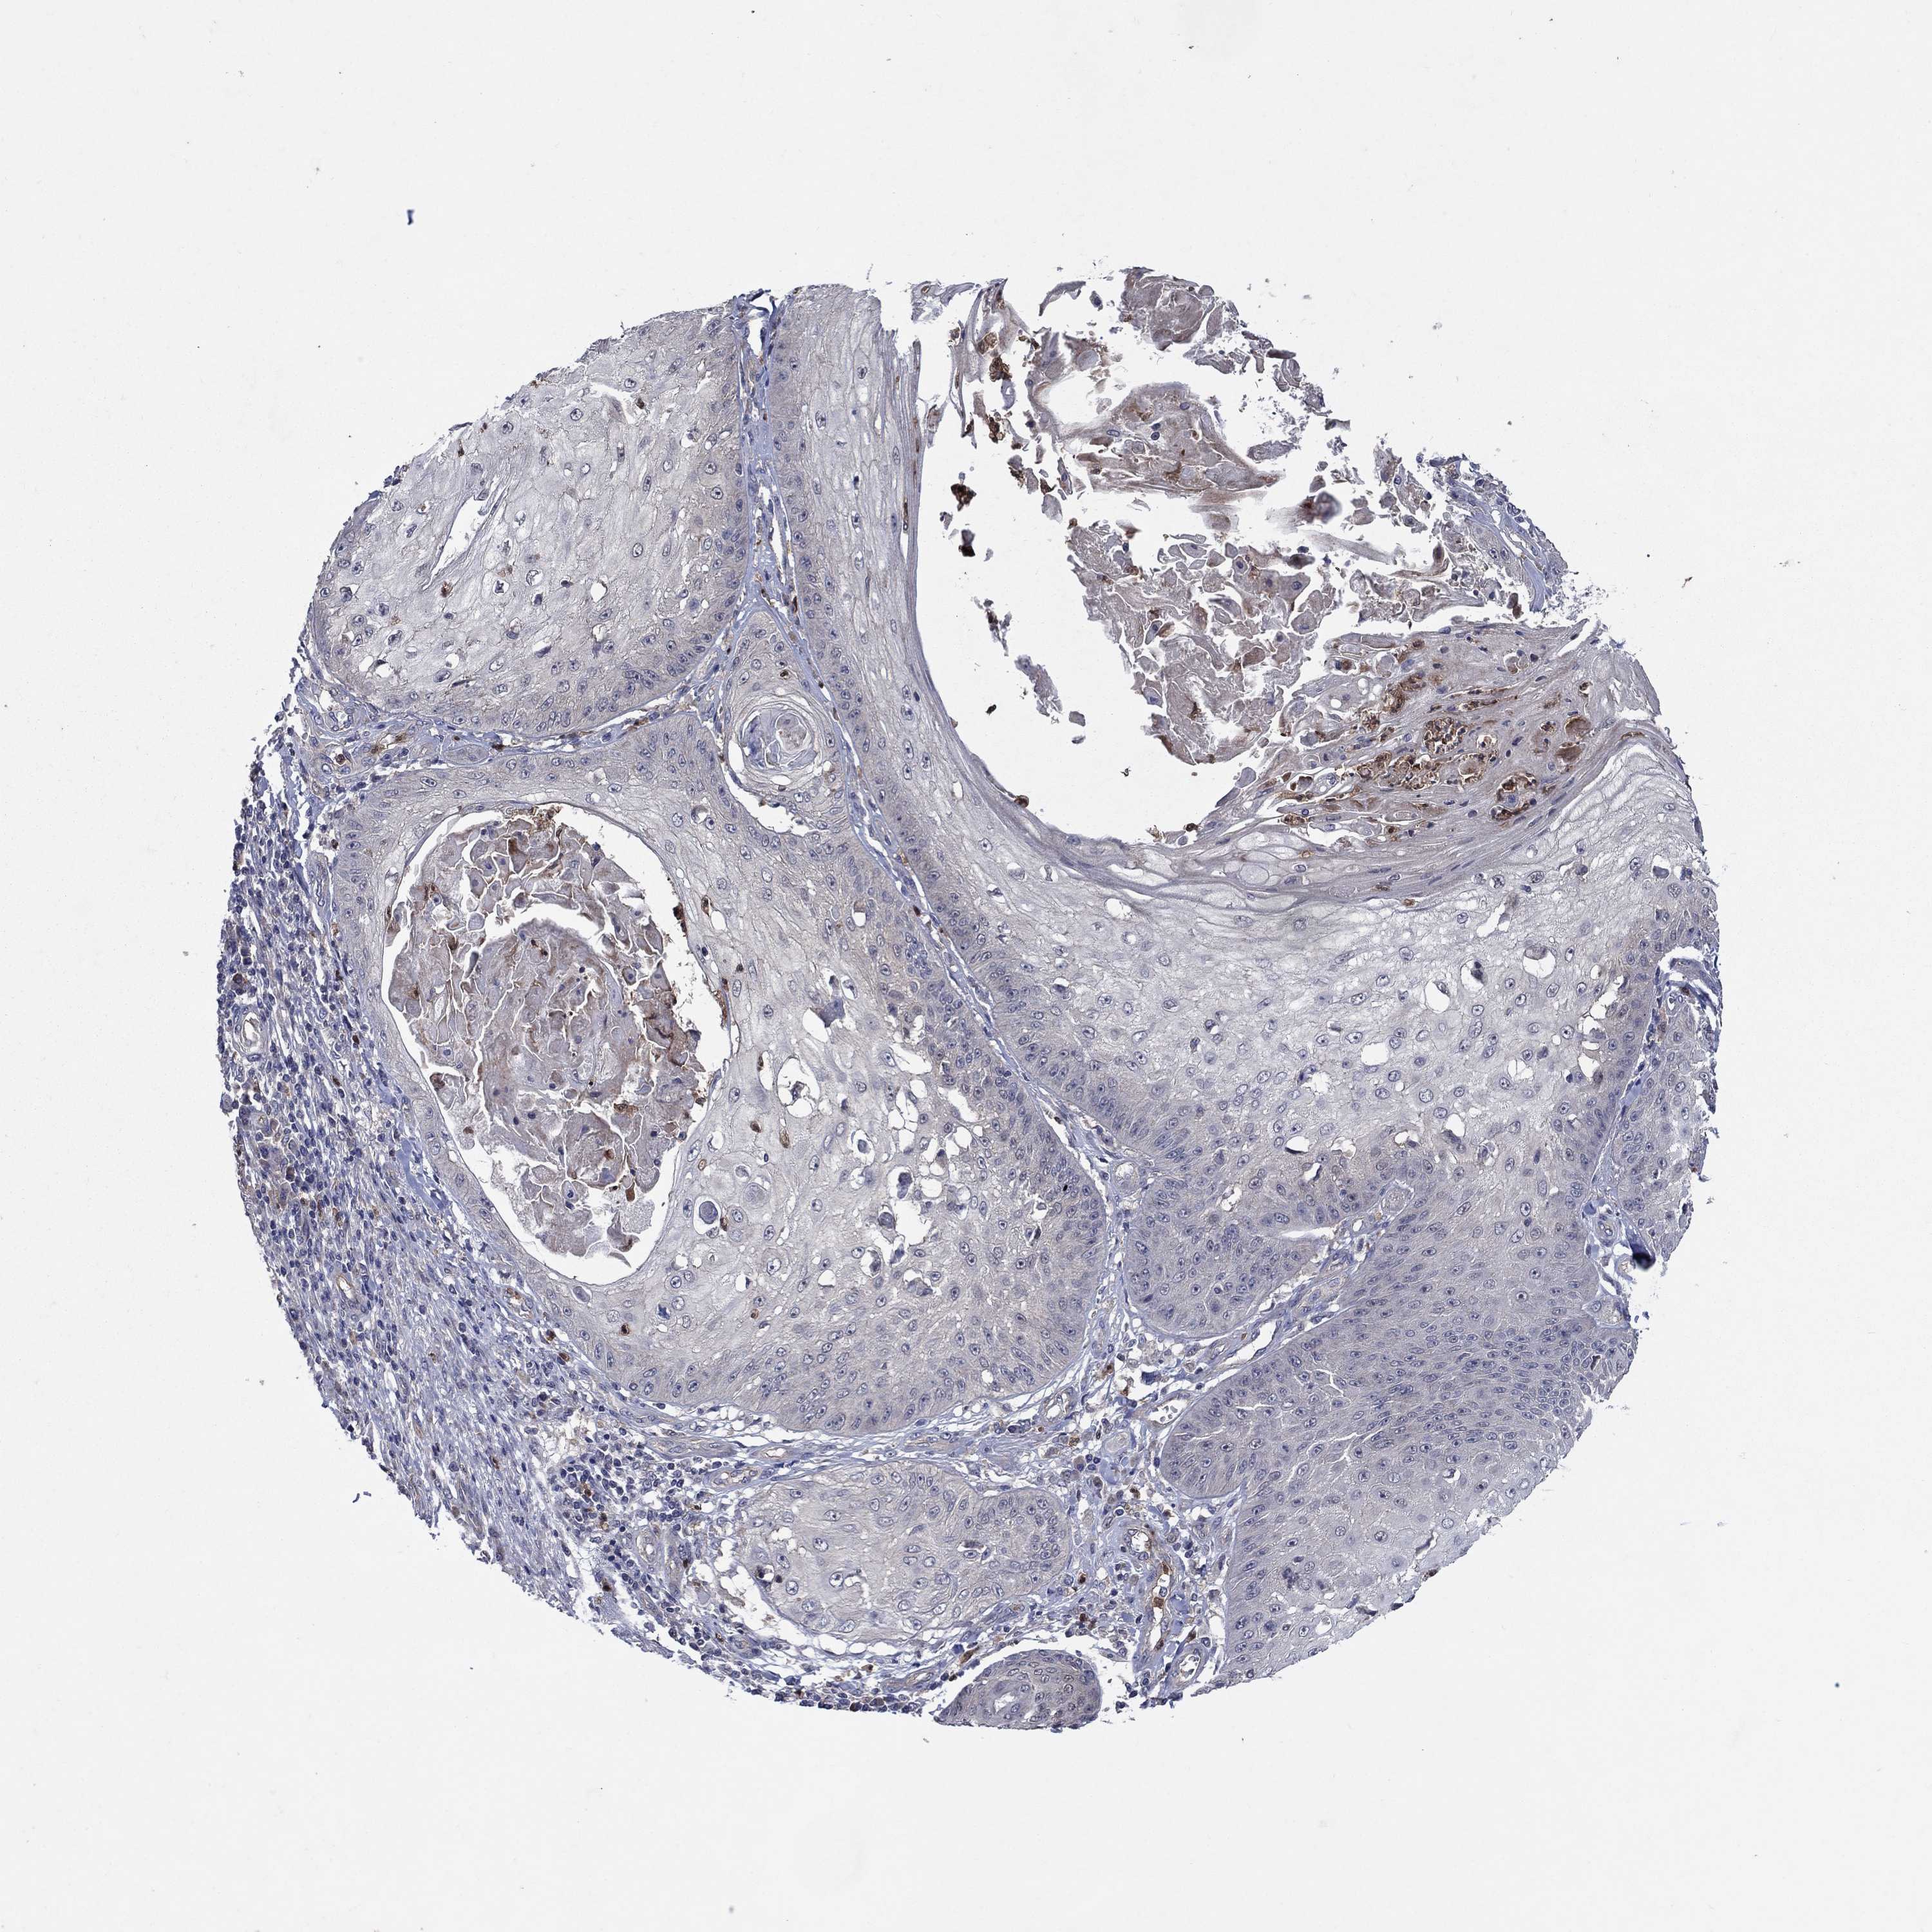

SKIN CANCER - Protein expressioni

A mouse-over function shows sample information and annotation data. Click on an image to view it in a full screen mode. Samples can be filtered based on level of antibody staining by selecting one or several of the following categories: high, medium, low and not detected. The assay and annotation is described here.

Antibody stainingi

Antibody staining in the annotated cell types in the current human tissue is reported as not detected, low, medium, or high, based on conventional immunohistochemistry profiling in selected tissues. This score is based on the combination of the staining intensity and fraction of stained cells.

Each image is clickable and will lead to virtual microscopy that enables deeper exploration of all samples and also displays staining intensity scores, fraction scores and subcellular localization as well as patient and tissue information for each sample.

Antibody HPA069557

Antibody CAB008650

Basal cell carcinoma

Squamous cell carcinoma, NOS